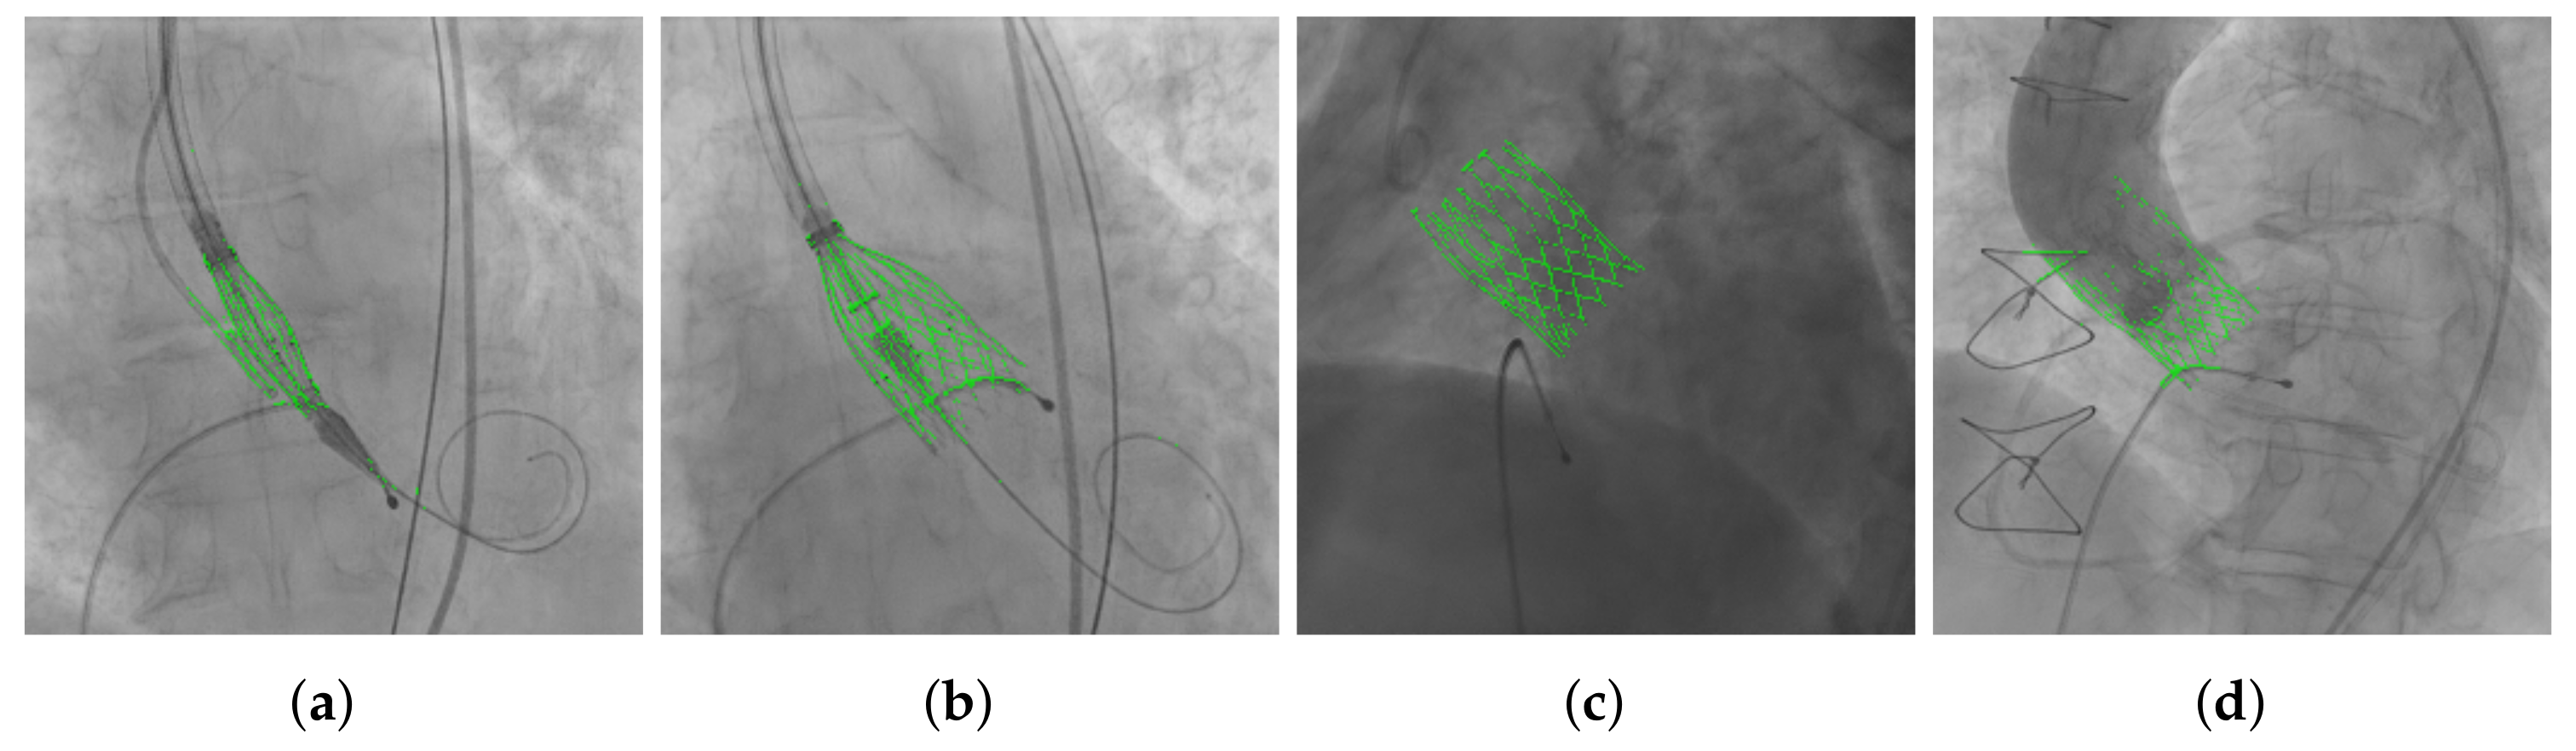

3.1. Image Acquisition and Annotation

3.3. THV Segmentation